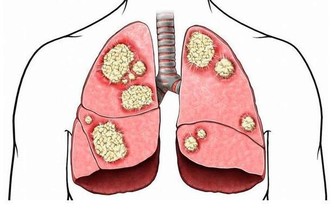

糖尿病是健康的無形殺手 糖尿病是健康的無形殺手,除了家族遺傳糖尿病外,台灣人飲食日漸西化、外食人口越來越多,又缺乏運動,不知不覺中造就了肥胖身材,糖尿病也會悄悄上身! 人只要一肥胖,就會產生胰島素阻抗,胰島素分泌的品質會變差,但為了維持血糖平衡,胰臟就得不斷加倍做工分泌胰島素,最後日漸衰退,再也無法分泌足夠的胰島素,血液中的血糖會因此上升,糖尿病就來報到了。 典型症狀: 多喝、多吃、多尿、體重減輕 很多糖尿病是吃出來的!近10年來,因飲食引起的糖尿病年齡有逐漸下降的趨勢。台北榮總新陳代謝科主治醫師石光中表示,現在門診中偶爾可看到11、12歲的糖尿病患,主要因為青少年偏好高熱量飲食,愛吃炸雞、薯條等油炸食物,也愛吃蛋糕、喝含糖飲料等甜食或糖化食物,還有在電腦前久坐、少運動,造成過度肥胖,因而年輕小胖子得到第2型糖尿病的人數是第1型的6倍之多。